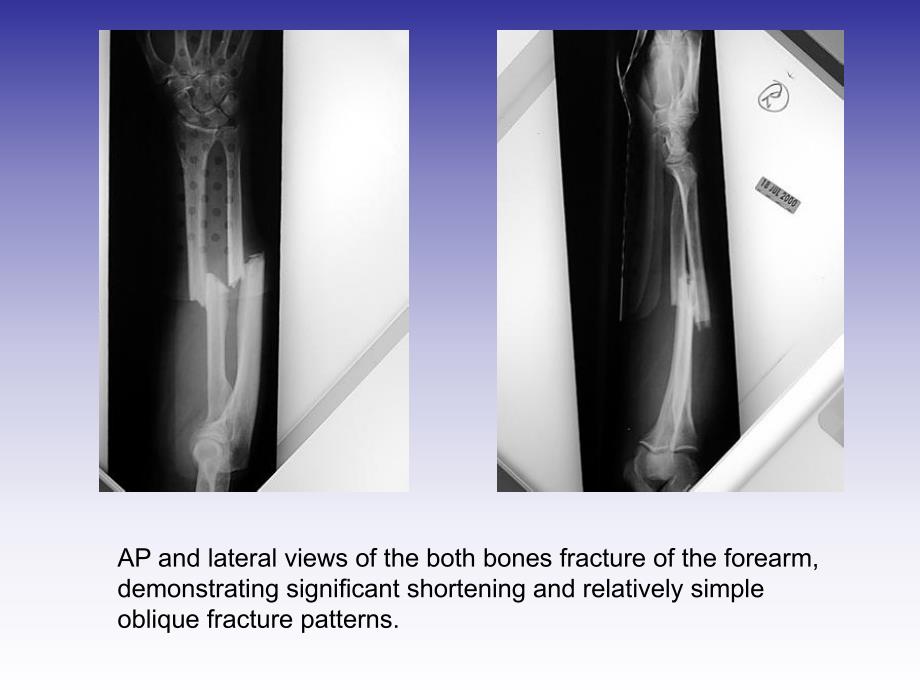

1、尺桡骨双骨折尺桡骨双骨折 骨二科学习AP and lateral views of the both bones fracture of the forearm,demonstrating significant shortening and relatively simpleoblique fracture patterns.The patient is positioned supine with the arm prepped anddraped to just above the elbow and a tourniquet in place.This figure demonstra